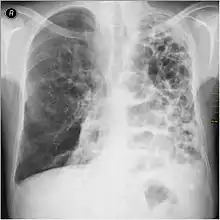

- Chest X-ray demonstrating severe COPD: Note the small heart size in comparison to the lungs.

- A lateral chest X-ray of a person with emphysema: Note the barrel chest and flat diaphragm.

- Lung bulla as seen on chest X-ray in a person with severe COPD

- A severe case of bullous emphysema

- Axial CT image of the lung of a person with end-stage bullous emphysema

- Very severe emphysema with lung cancer on the left (CT scan)

A chest X-ray and complete blood count may be useful to exclude other conditions at the time of diagnosis.[82] Characteristic signs on X-ray are hyperinflated lungs, a flattened diaphragm, increased retrosternal airspace, and bullae, while it can help exclude other lung diseases, such as pneumonia, pulmonary edema, or a pneumothorax.[83] A high-resolution CT scan of the chest may show the distribution of emphysema throughout the lungs and can also be useful to exclude other lung diseases.[25] Unless surgery is planned, however, this rarely affects management.[25] A saber-sheath trachea deformity may also be present.[84] An analysis of arterial blood is used to determine the need for oxygen; this is recommended in those with an FEV1 less than 35% predicted, those with a peripheral oxygen saturation less than 92%, and those with symptoms of congestive heart failure.[24] In areas of the world where alpha-1 antitrypsin deficiency is common, people with COPD (particularly those below the age of 45 and with emphysema affecting the lower parts of the lungs) should be considered for testing.[24]